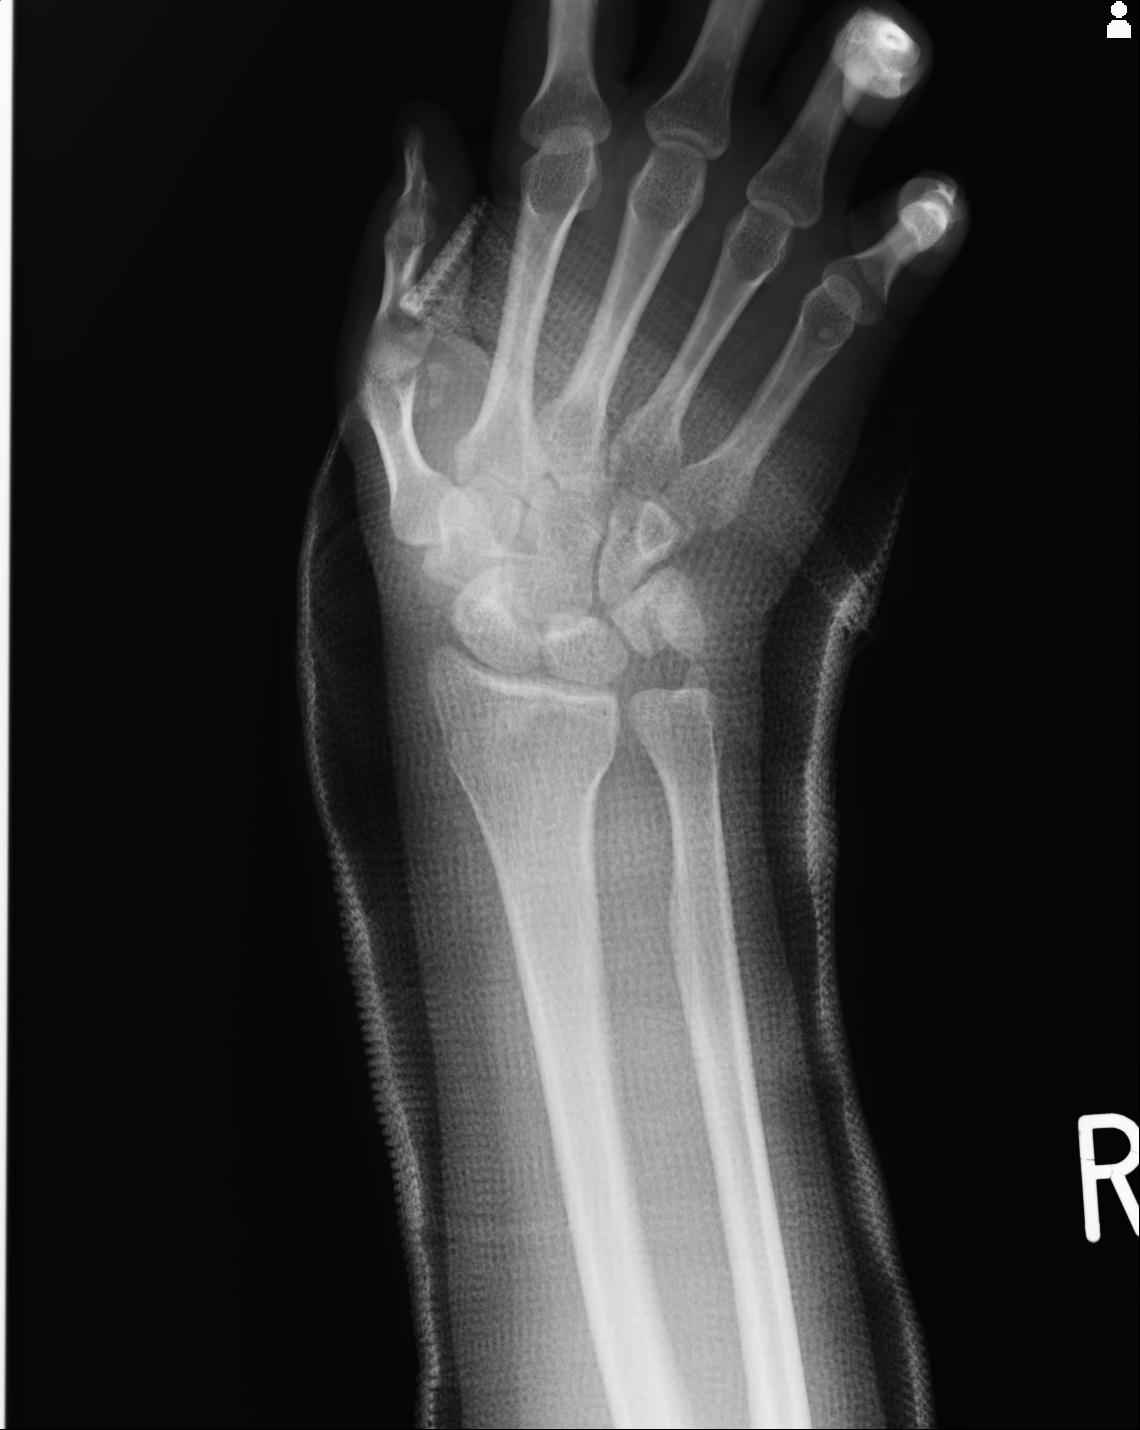

46666 1/23 両股正面+軸と右手関節 2R 76歳女性 右橈骨遠位端

50435 1/4 1/15 手関節 4R 17歳女性 右橈骨遠位端

102739 12/30 1/5 左手関節 4R 92歳女性 橈骨遠位端

101290 1/4 5/21 5/20 手関節 2R 17歳男性 橈骨遠位端